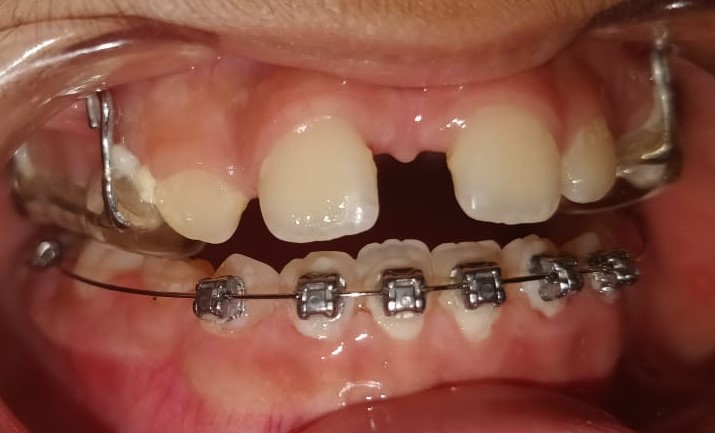

7) Manvir – Tongue Thrusting habit breaking appliance